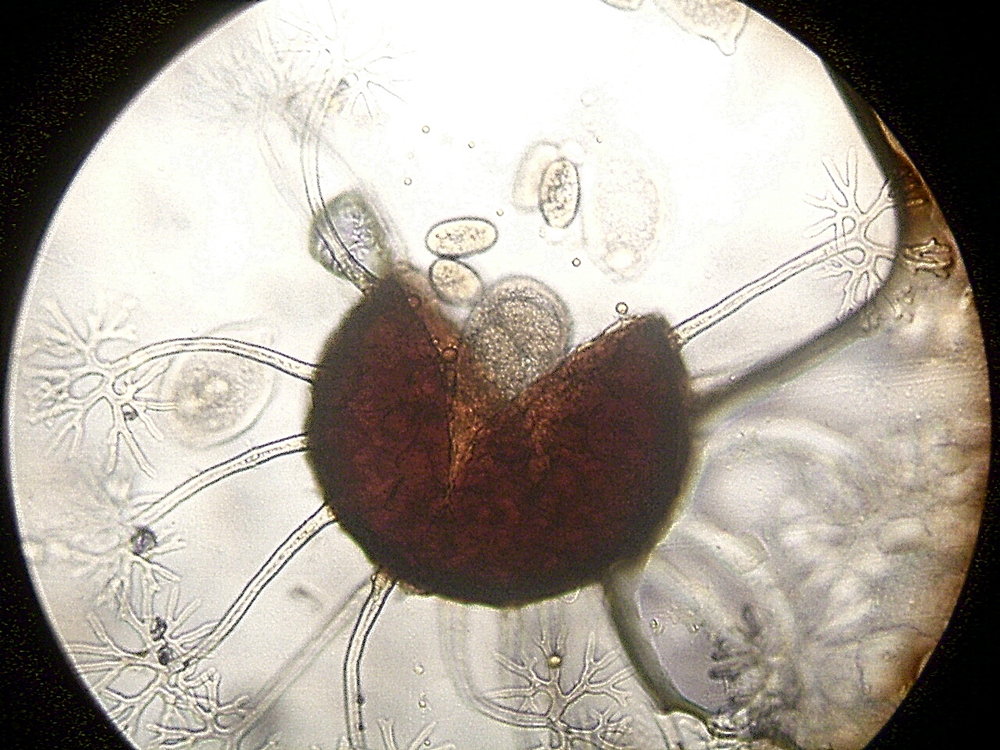

Guten Abend zusammen! Pilze - aber mal an Stellen wo sie nicht sein sollen:

Aspergillus sp. in einem Erguss. (PAS Färbung).

Pilzorganismen - Wahrscheinlich Hefen, invasiv in einem abgestorbenen Blutgefäß der Bronchialschleimhaut. (PAS)

Aspergillus, nicht invasiv aus dem Bronchialsystem. (PAS) Zusammen mit Schleim und Bronchusepithelien (Oben links bei ca. 11 Uhr)

Konidiophor zum Fall oben. Sieht man recht selten. (HE)

Pilzbestimmung in der Histologie ist selten Zielführend da bestimmungsrelevante Merkmale entweder nicht auftauchen (bzw. nicht vollständig abgebildet sind) oder die Morphologie nicht immer typisch ausgeprägt ist. Wenn nötig (z.B. wenn bei einem Zufallsbefund kein Material an die Mikrobiologie gegangen ist) wird sequenziert. Schimmelpilz vs. Hefe ist erstmal das höchste der Gefühle.

Arbeitstiere der Färbungen sind neben PAS auch PAS nach Diastase Verdau (D-PAS) und Versilberung nach Grocott (beide Zeige ich gerne wenn entsprechende Präparate vorbei kommen).